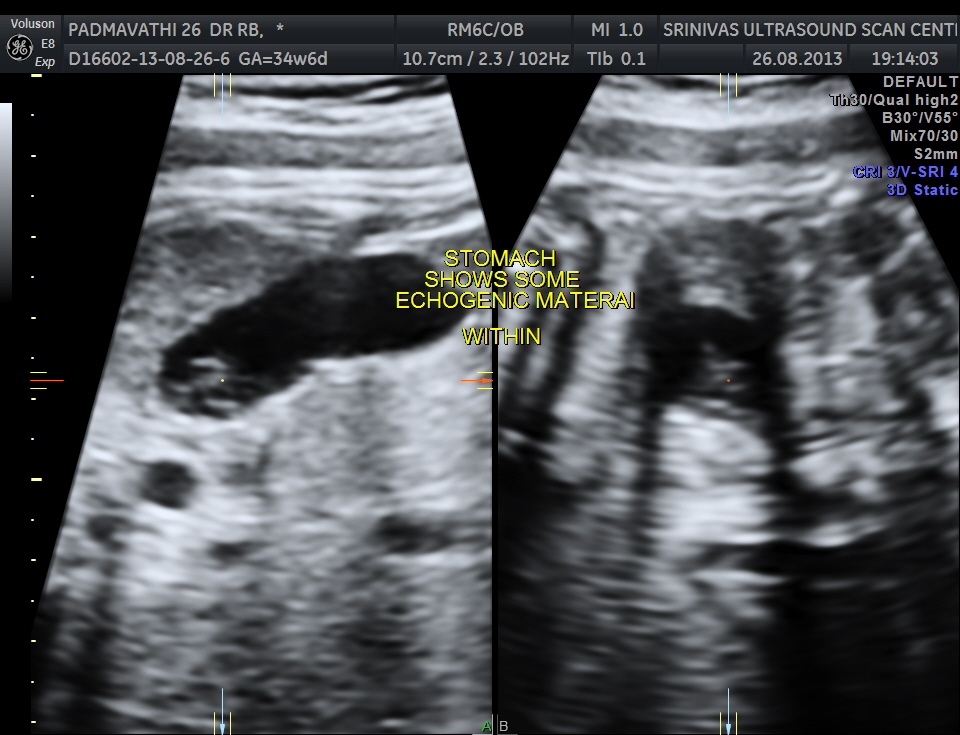

Echogenic material is seen within the stomach.

The following are 3 d images , which prove that this was not an artefact.

At US examination from the second trimester onward, the fetal stomach appears as a uniformly anechoic, sharply circumscribed round structure in the left upper quadrant. However, debris is commonly visualized in the stomach, forming a pseudomass.

The origin of echogenic masses within the gastric lumen is incompletely understood. As they are seen in multiple planes, technical issues are unlikely. They may be due to swallowed cells that aggregate because of the relatively poor peristaltic activity in the stomach early in the second trimester . When intraamniotic bleeding has occurred, these pseudomasses are commonly visualized. They inevitably disappear during follow-up examinations and are not associated with an adverse neonatal outcome. Therefore, further evaluation of this finding is not required.